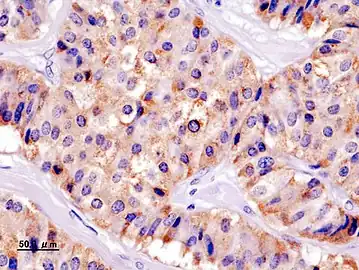

| Pathology of pancreatic endocrine tumour (insulinoma). | |

Insulin immuostain